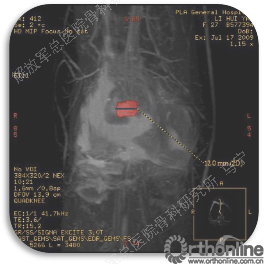

首先经过核磁的检查、评估,初步确定软骨损伤范围,利用T2maping检测序列对软骨的信号区分。图中我们可以看到软骨损伤的范围,并通过计算机计算出大概的面积。

软骨缺损范围的测量。

姜**:男,33岁 ,双膝疼痛,活动受限1年,曾经打过玻璃酸钠,效果都不理想,来我院行软骨修补术,MRI显示髌骨软骨下骨增生明显,并开始磨损滑车。

术后3个月在当地医院复查MRI,软骨补片与正常软骨还存在GAP现象,冠状位隐约还能看见周围的轮廓。

术后6个月复查MRI,软骨修复的已经具备一定的厚度,软骨下骨没有明显水肿。增生的软骨下骨被去除后没有再进一步磨损滑车软骨。